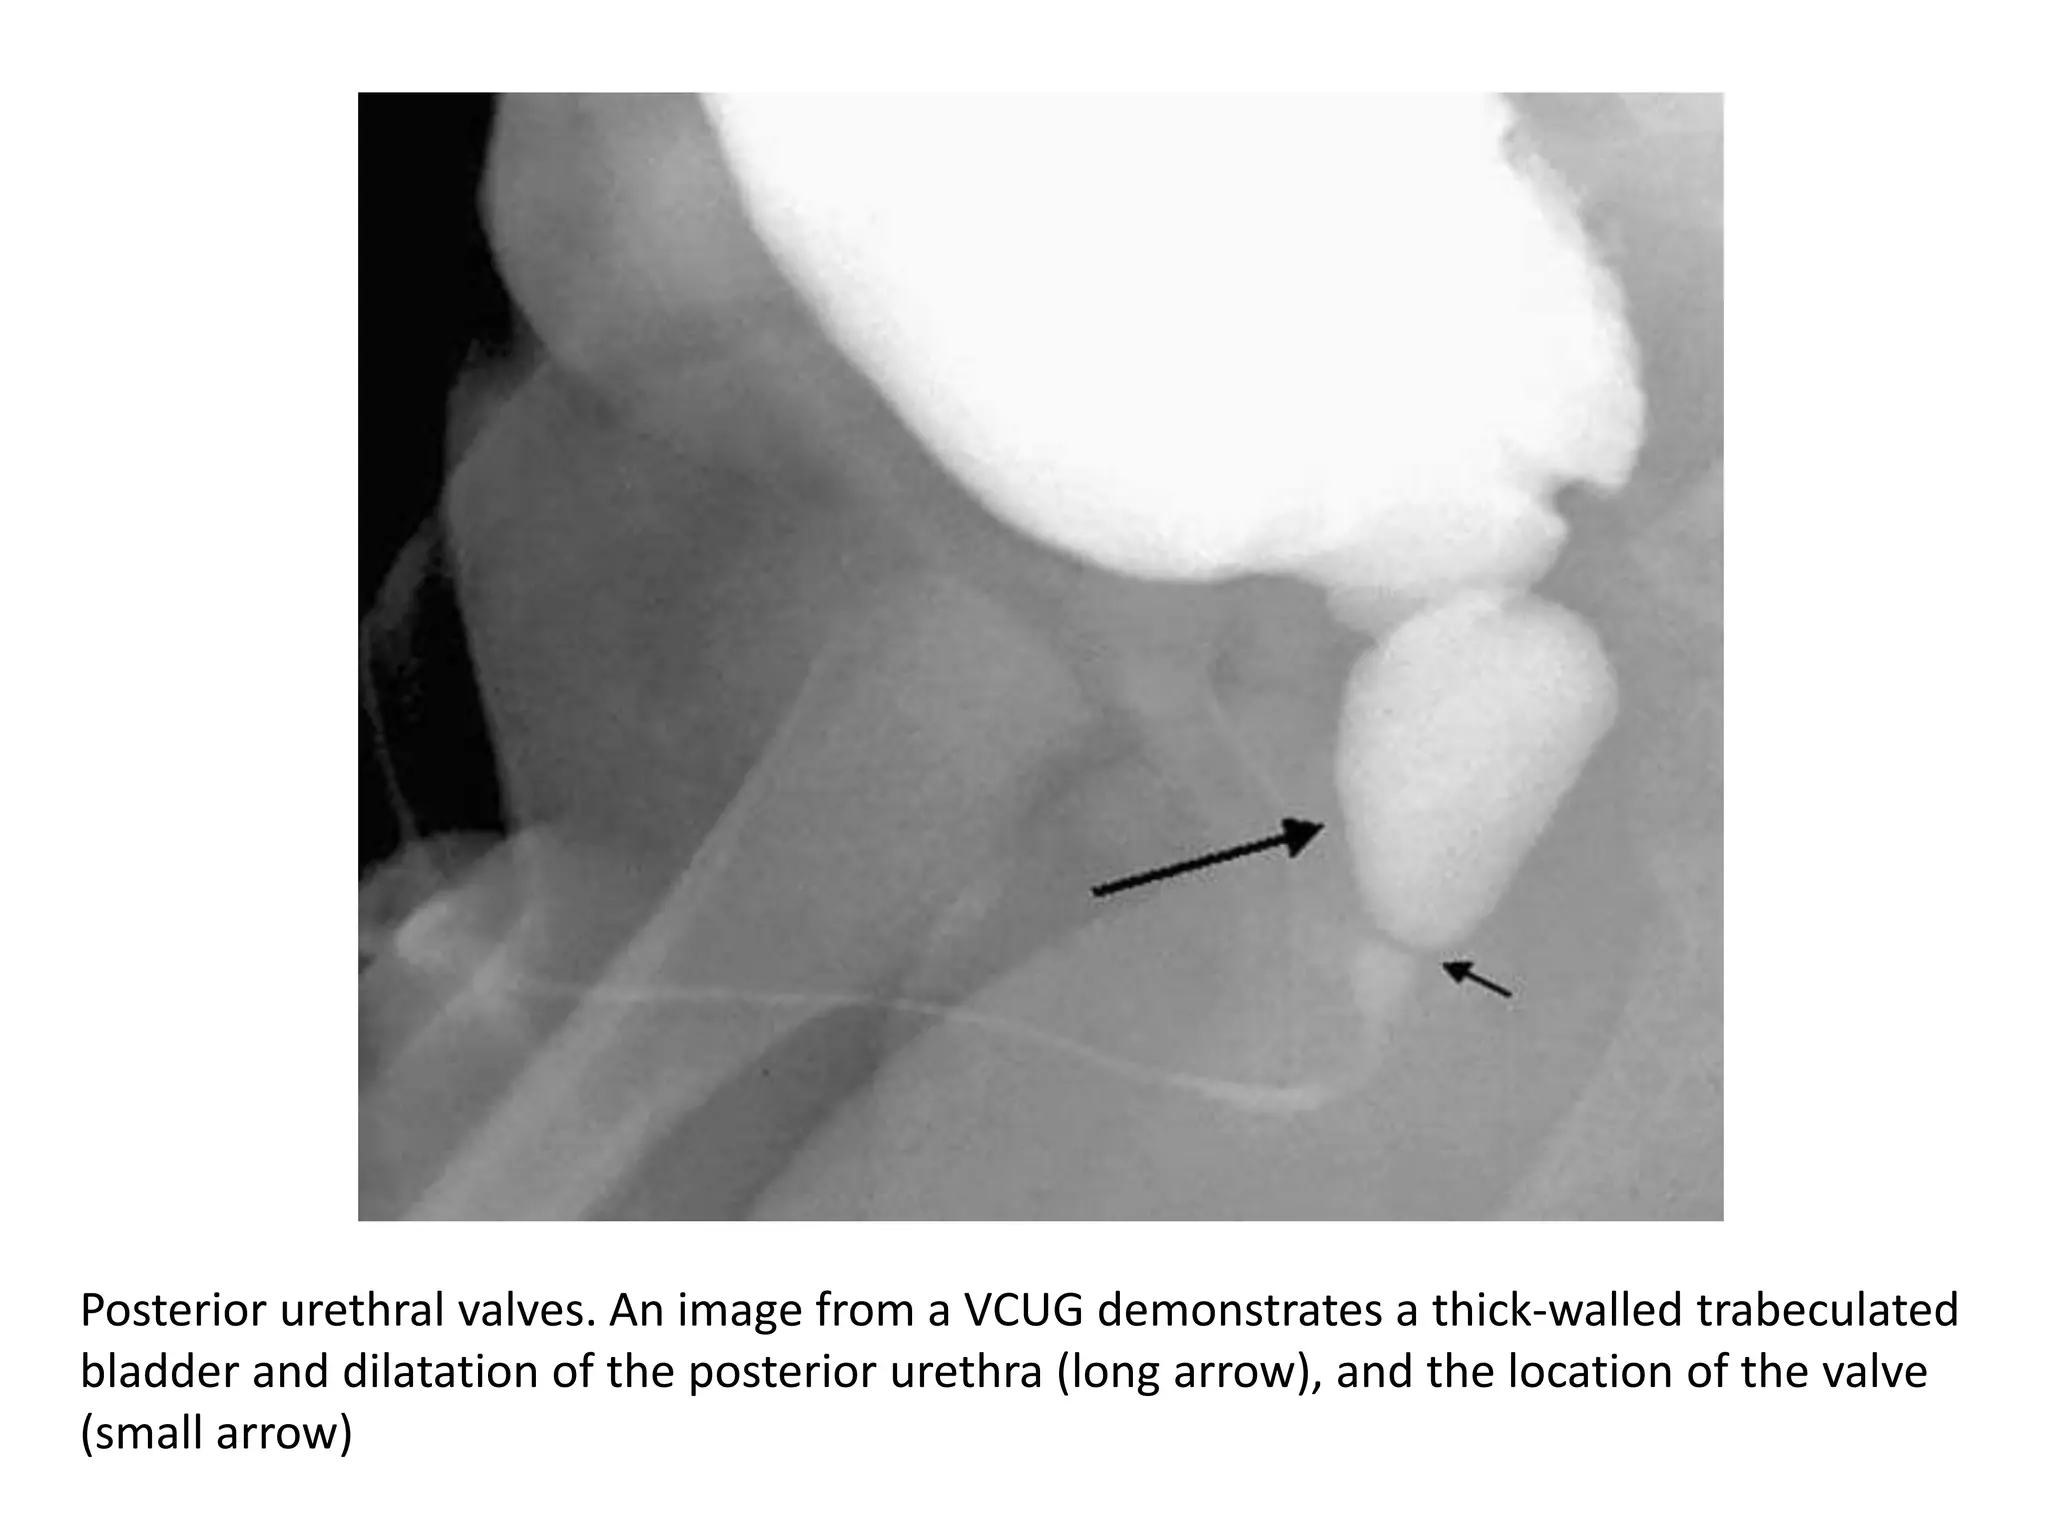

• Radiologic findings include dilatation and

elongation of the posterior urethra and,

occasionally, a linear radiolucent band

corresponding to the valve.

• The bladder neck becomes hypertrophic and

appears narrow in relation to the dilated

posterior urethra.

• VUR occurs in 50% of patients.

• Bladder trabeculation, hypertrophy, and

diverticula are also demonstrated at VCUG

Posterior urethral valves. An image from a VCUG demonstrates a thick-walled trabeculated

bladder and dilatation of the posterior urethra (long arrow), and the location of the valve

(small arrow)

Posterior urethral valves.An image from a VCUG demonstrates a thick-walled trabeculated bladder and dilatation of the posterior urethra (long arrow), and the location of the valve (small arrow)